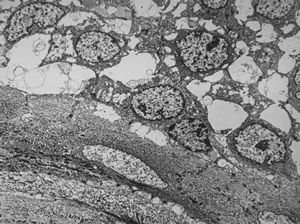

F,42y. | pseudoangiomatous hyperplasia

F,42y. | pseudoangiomatous hyperplasia

F,42y. | pseudoangiomatous hyperplasia

F,42y. | pseudoangiomatous hyperplasia

F,42y. | pseudoangiomatous hyperplasia